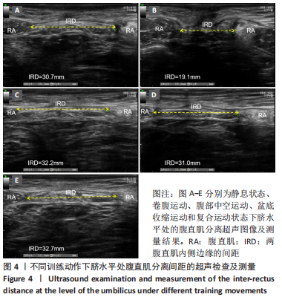

[9] MOTA P, PASCOAL AG, CARITA AI, et al. The immediate effects on inter-rectus distance of abdominal crunch and drawing-in exercises during pregnancy and the postpartum period. J Orthop Sport Phys. 2015;45(10):781-788.

[10] PASCOAL AG, DIONISIO S, CORDEIRO F, et al. Inter-rectus distance in postpartum women can be reduced by isometric contraction of the abdominal muscles: a preliminary case–control study. Physiotherapy. 2014; 100(4):344-348.

[11] THEODORSEN NM, STRAND LI, BØ K. Effect of pelvic floor and transversus abdominis muscle contraction on inter-rectus distance in postpartum women: a cross-sectional experimental study. Physiotherapy. 2019;105(3):315-320.

[28] SANCHO MF, PASCOAL AG, MOTA P, et al. Abdominal exercises affect inter-rectus distance in postpartum women: a two-dimensional ultrasound study. Physiotherapy. 2015;101(3):286-291.